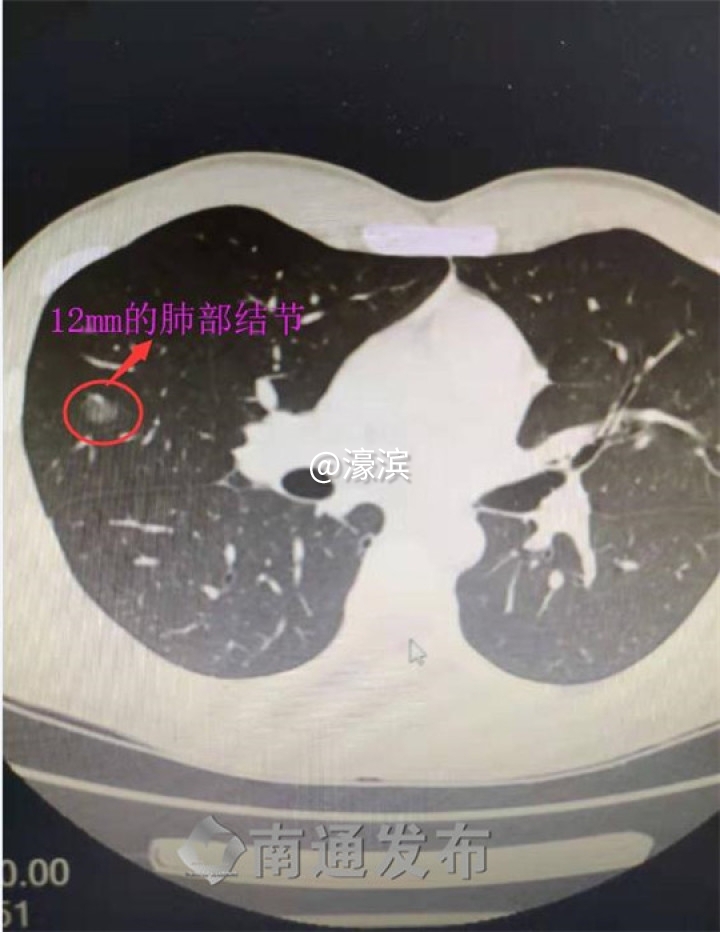

入职体检无意查出两肺结节,最大的12mm

26岁的小伙子小王前些天因为要入职,来到南通市第六人民医院做入职体检。巧的是,那几天他正在感冒,有一周了,还伴有咳嗽一周不见好,他的一个亲戚是医生,就让他在入职常规体检的基础上再增加做一项肺部CT检查。小伙子说,行!CT扫描结果让医生都紧张,小伙子两肺都有结节,其中右中肺上的结节有12mm。根据形态观察,医生怀疑“肺癌可能”,这让他顿觉“怀疑人生”。